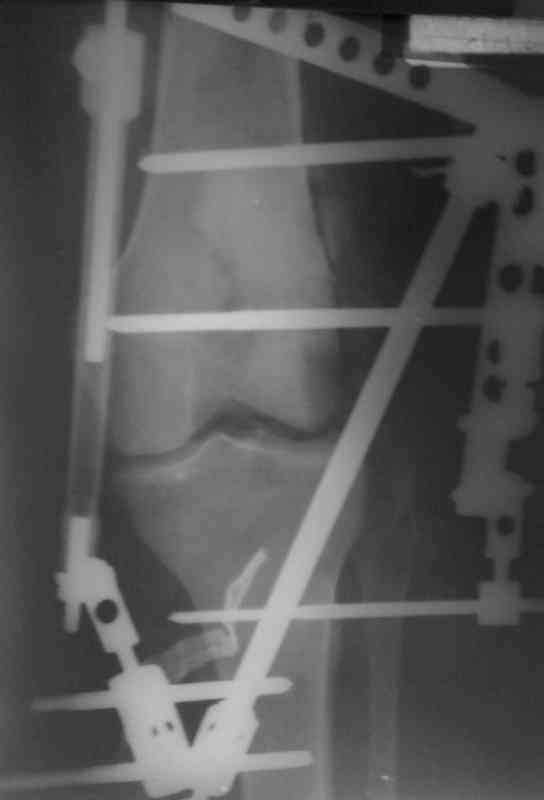

Снимки прошлых публикации из моего Power point

Аппарат внешней фиксации удаляется в 6-7 недель,

предпочтительно под общим обезболиванием, во время

удаления проверяется стабильность и амплитуда движения в коленном суставе с редрессацией.

Последующее два-три месяцев проводим ЛФК сустава,

потом на основании стабильности сустава решается

необходимость оперативного вмешательства.

Общепринятые последовательности реконструкции,

поэтапные восстановление PCL плюс медиальная или PCL плюс латеральная, хотя множество случаев когда связки срастались в течение 6-7 недель, больные восстанавливали движения сустава без оперативного вмещательства.